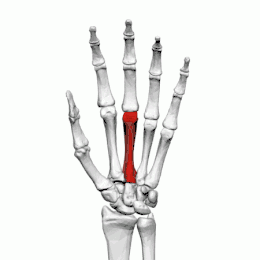

Les métacarpiens (ou os métacarpiens ou os du métacarpe) sont les os formant le métacarpe squelette de la paume de la main. Ils sont articulés dans leur partie supérieure[1] avec les os de la rangée distale du carpe et se prolonge au niveau de sa partie inférieure[1] par les phalanges proximales. Ces os sont unis par les muscles interosseux.

Les métacarpiens sont cinq petits os longs numérotés de 1 à 5, de dehors en dedans en position anatomique : 1 correspond au pouce et 5 à l'auriculaire. Chacun se compose d'une base proximale, d'un corps et d'une tête distale.